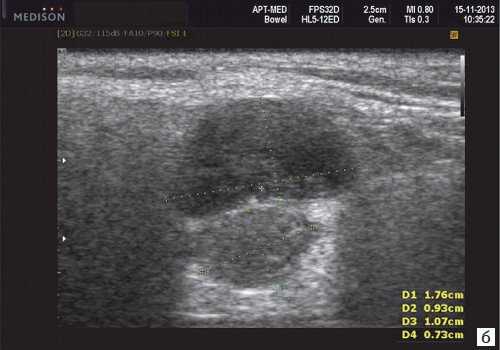

Плеоморфная (полиморфная) аденома (смешанная опухоль СЖ) - аденома СЖ, построенная из двух типов клеток: эпителия протоков и миоэпителиоцитов. Макроморфологическая картина. Опухоль обычно представляет собой эластичный или плотный узел дольчатой серовато-белой ткани, как правило, инкапсулированный частично. Типичной для плеоморфной аденомы является так называемая хондроидная строма, напоминающая гиалиновый хрящ. Варианты эхографического изображения плеоморфных аденом представлены на рисунке 8.